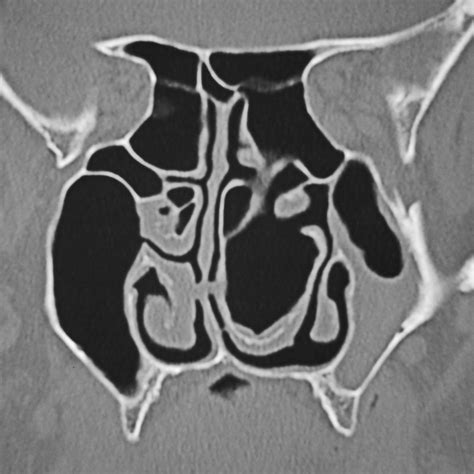

When an air cell develops within the middle turbinate, the structure expands significantly. This expansion is the defining characteristic of a Concha Bullosa. Depending on the size of the air pocket, the enlarged turbinate can press against the nasal septum or the lateral nasal wall, effectively narrowing the nasal passage and obstructing the narrow drainage pathways, known as the ostiomeatal complex, where the sinuses drain into the nose.

Diagnosing a Concha Bullosa typically requires more than a simple visual inspection during a physical exam. While an ENT might suspect the condition using an endoscope—a thin, flexible tube with a camera—a definitive diagnosis almost always relies on imaging. A Computed Tomography (CT) scan of the paranasal sinuses is the gold standard. It provides a detailed cross-sectional view of the nasal architecture, allowing the physician to measure the exact size of the air pocket and determine if it is contributing to sinus obstruction.

CT Scan Detailed imaging to confirm pneumatization and identify potential obstruction sites.